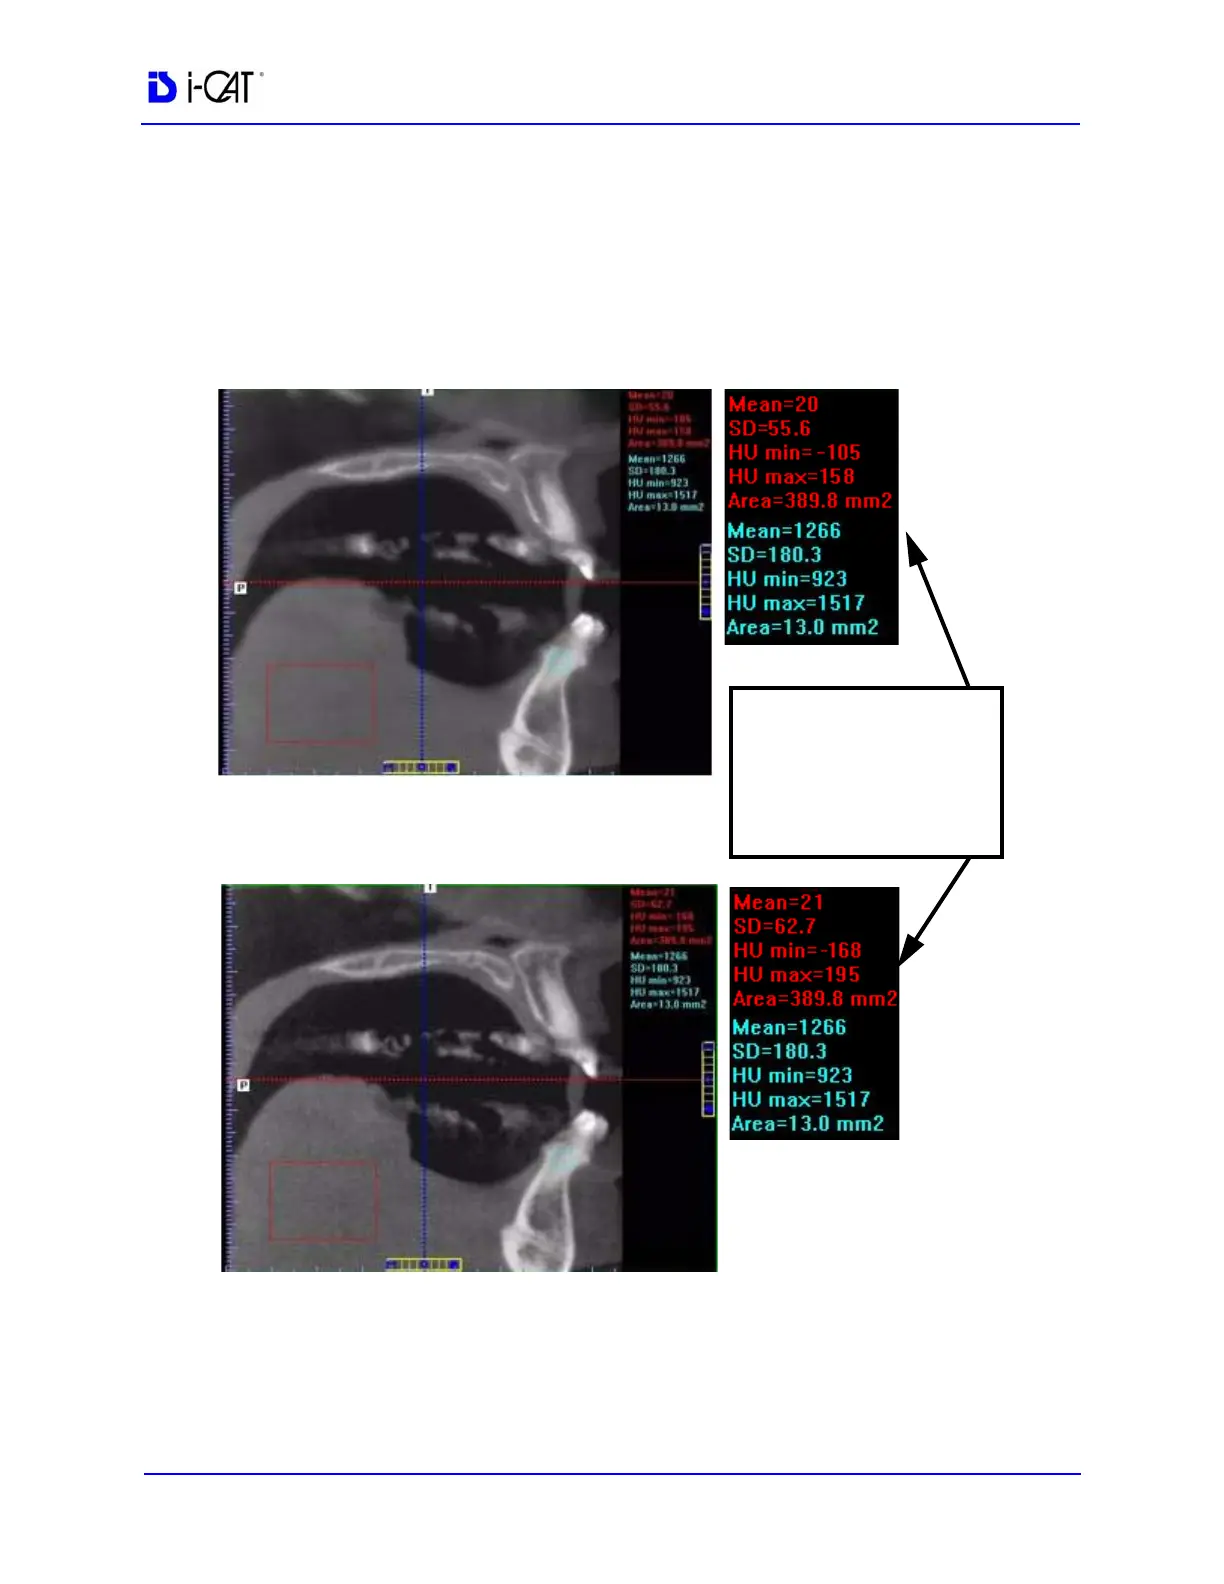

Quantum IQ is an image processing option that may be performed

on an image volume when it is reconstructed. Quantum IQ smoothes

out the noise in the soft tissue areas.

Standard Deviation (SD)

values in soft tissue (red)

decrease with Quantum

IQ applied.

Bone (blue) remains

Quantum IQ applied

Soft tissue appears smooth

Quantum IQ not applied

Soft tissue contains more noise

the same.